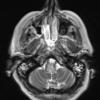

MYELIN (IMMUNE-MEDIATED)

Inflammatory Demyelination (19)